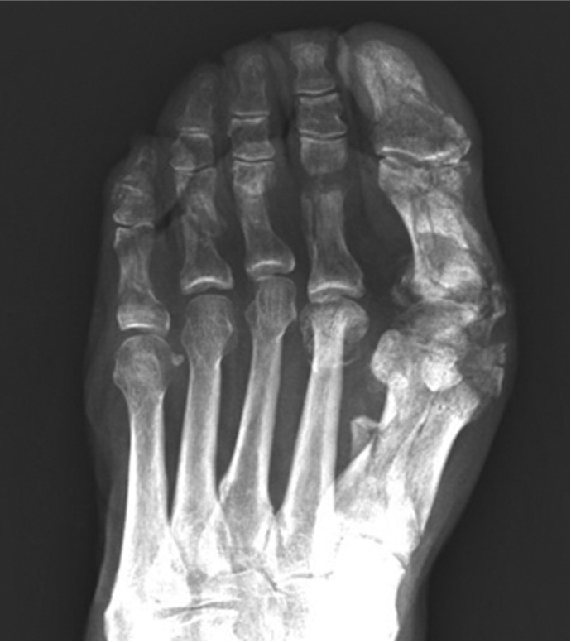

有護趾片保護

從上圖可見,有護趾片保護的情況下,重物不會直接撞擊到腳趾,因此骨頭仍是完好無損。

無護趾片保護

無護趾片保護的腳趾,直接被重物撞擊,可發現五隻腳趾的骨頭均被壓傷變形,大拇趾甚至已有粉碎性骨折。